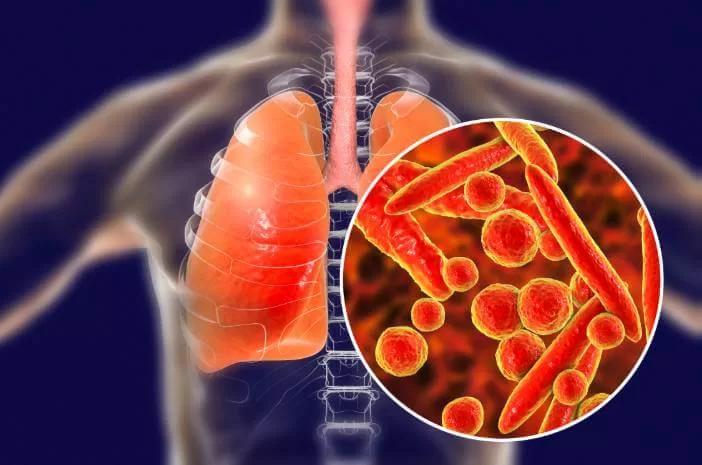

2. Tuberkulosis (TBC)

Tuberkulosis atau TBC merupakan penyakit spesifik yang disebabkan oleh bakteri Mycobacterium tuberculosae. Bakteri ini dapat menyerang semua organ tubuh, tetapi yang paling sering adalah paru-paru dan tulang.

Penyakit TBC menyebabkan proses difusi oksigen yang terganggu karena adanya bintik-bintik kecil pada dinding alveolus. Keadaan ini menyebabkan peningkatan kerja sebagian otot pernapasan yang berfungsi untuk pertukaran udara paru-paru, mengurangi kapasitas vital dan kapasitas pernapasan, mengurangi luas permukaan membran pernapasan, yang akan meningkatkan ketebalan membran pernapasan sehingga menimbulkan penurunan kapasitas difusi paru-paru.

5. Pneumonia

Pneumonia adalah peradangan paru-paru dimana alveolus biasanya terinfeksi oleh cairan dan eritrosit berlebihan. Infeksi disebarkan oleh bakteri dari satu alveolus ke alveolus lain hingga dapat meluas ke seluruh lobus bahkan seluruh paru-paru. Umumnya disebabkan oleh bakteri Streptococcus, Diplococcus pneumoniae, dan bakteri Mycoplasma pneumoniae.